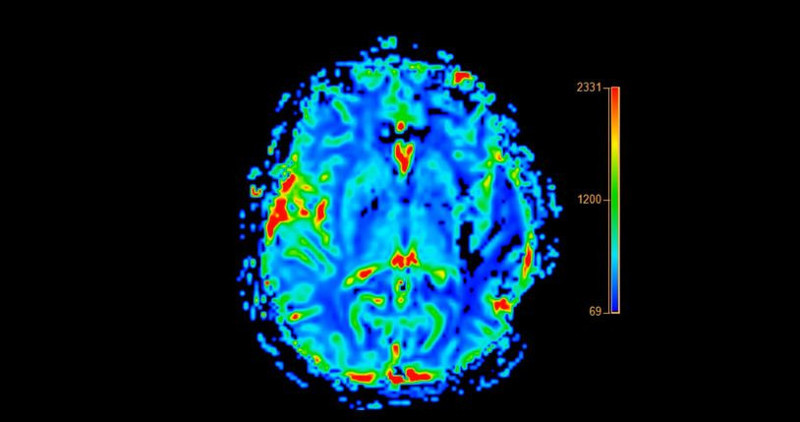

İşte erken yaşta alzheimer hastalığının 30 belirtisi...

Araştırmacılar yakalanma yaşı için 50'ye kadar düşen bir hastalıkla ilgili önemli uyarı verildi.